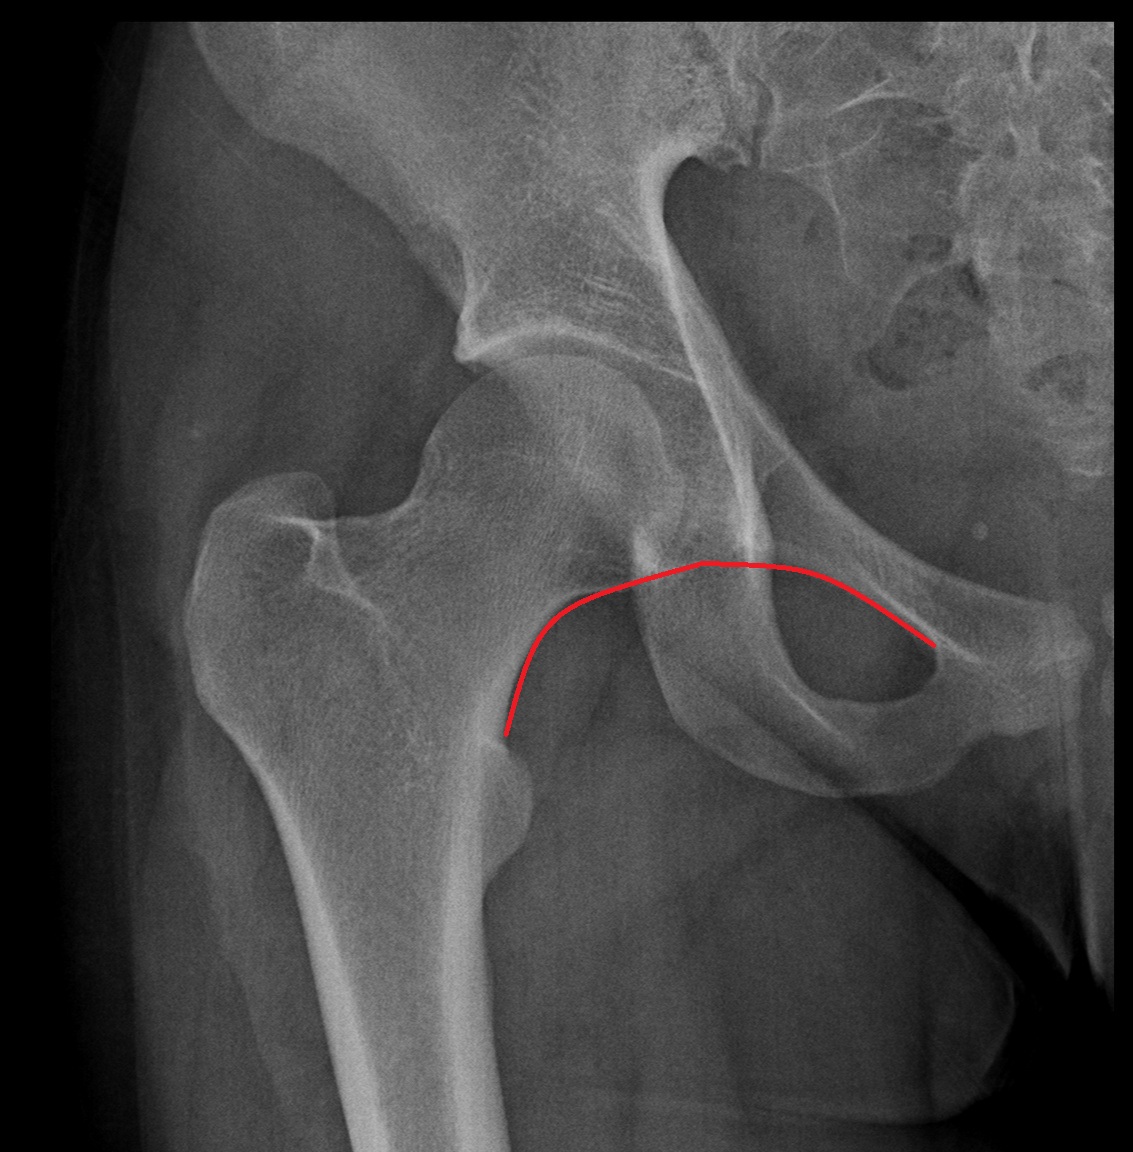

Shenton’s line

Shenton’s line is an imaginary smooth curved line you trace on an AP pelvis/hip X-ray:

• It runs along the inferior border of the superior pubic ramus

• and should continue seamlessly along the inferomedial border of the femoral neck

In a normal hip, it forms a continuous arc.

If it’s broken/stepped/disrupted, it suggests abnormal hip alignment, commonly seen with things like:

• Femoral neck fracture

• Hip dislocation/subluxation

• Developmental dysplasia of the hip (DDH) (especially in pediatrics)

• Slipped capital femoral epiphysis (SCFE) (teens)